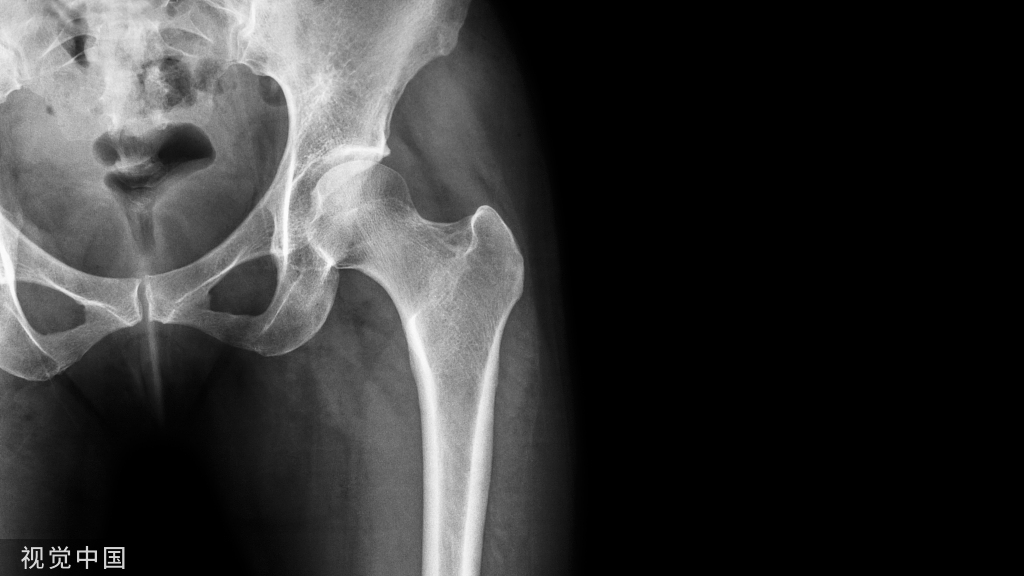

众所周知,腰椎节段动脉(3-4对)从腹主动脉发出,分段沿椎体侧壁对称排列,主要供应腰椎、椎旁肌和腹后壁的肌肉,静脉同动脉伴行,也遵循相应的规律。但是这篇文章的作者通过尸体解剖,认为这种观点并不完全正确。其研究证实了腰椎节段动脉成对排列,很少缺席,最常见的是三对腰动脉(86%),常见的变异有骶骨中动脉与第四腰动脉形成三叉分支,这种变异往往伴随腰动脉的位置较正常水平偏低,如下图所示。